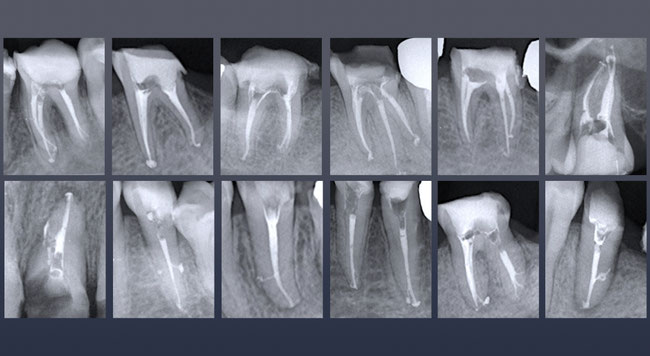

根の治療で治らない歯がある方や、抜歯してブリッジ、入れ歯と言われた方で不要な親知らずがある方にとっていい治療法となるかもしれません。ご参照ください。

かぶせものの精度は的確か、歯石の取り残しはないか、根の中はどうなっているのか、すべて口の中を見ただけでは分かりません。患者さんには分からない箇所であるからこそ、そこにこだわった歯科医院でありたいと思います。自分の行った治療の経過を追うこと以外にいい歯科医になる方法はないと信じております。お口の中の写真を撮ってもらったことはありますか?治療の必要性を、予後を説明されたことはあるでしょうか?当院では記録を大事にし治療の経過を追いかけてより良い医療を提供しようと考えております。